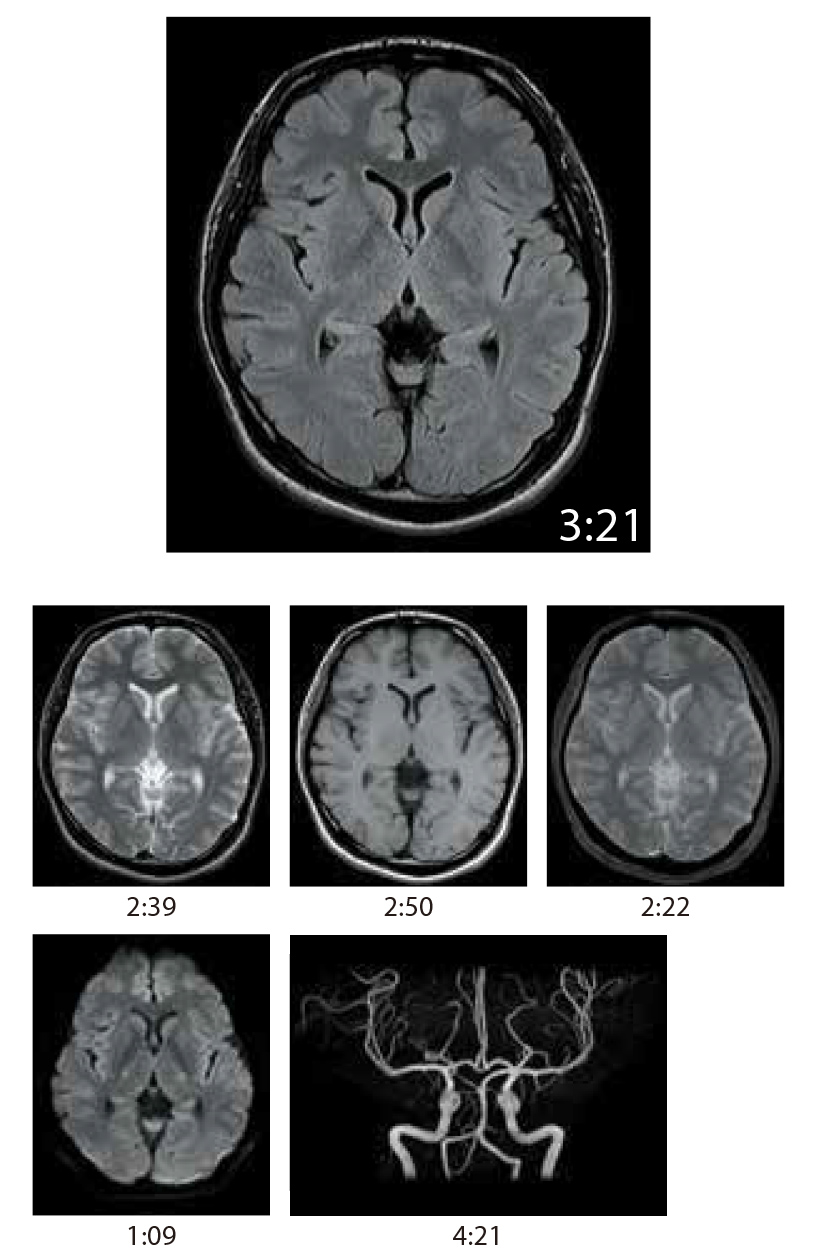

IP-RAPID is high-speed imaging using iterative processing, reducing scan times by up to 60% while maintaining image quality comparable to conventional imaging methods that don't apply IP-RAPID.

IP-RAPID is a technology that can reduce scan time while maintaining image quality.

By combining undersampling and iterative reconstruction, it can be combined with various regions and functions.

SNR and spatial resolution can also be improved while maintaining the scan time.

Value is compared between the following examples